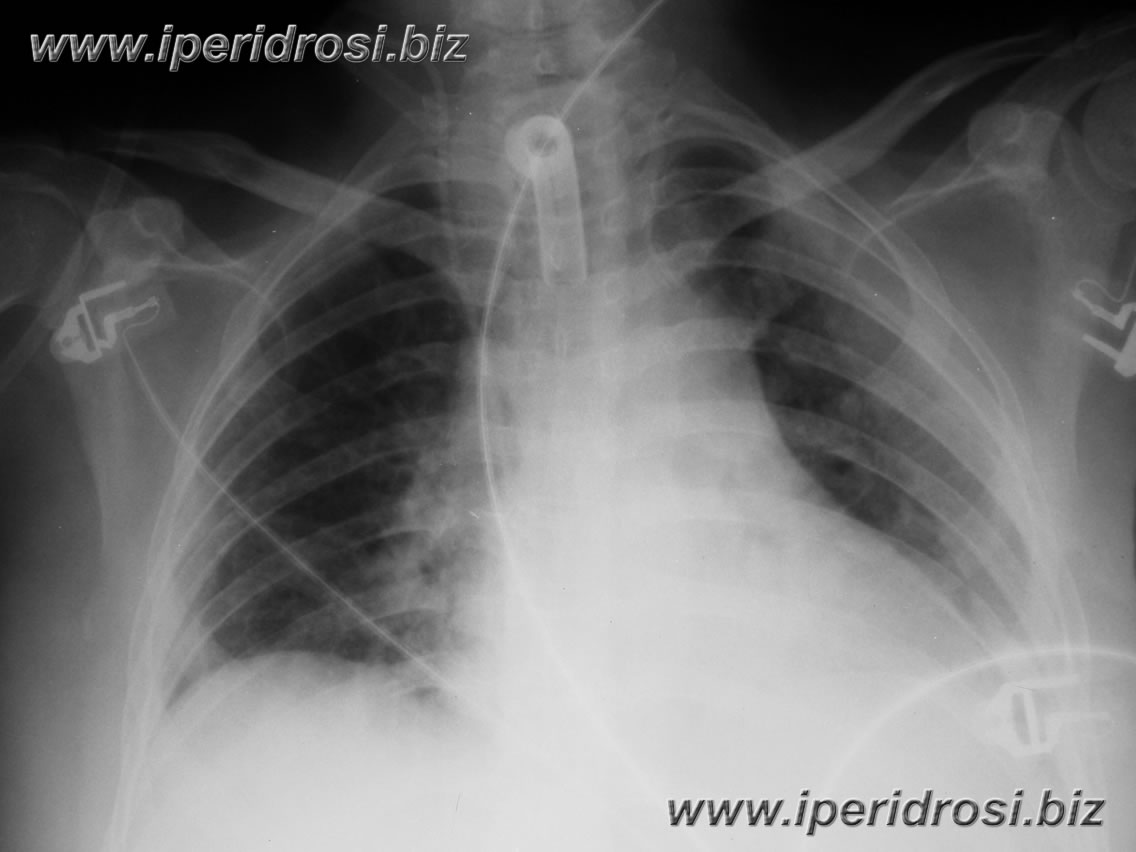

esegue Rx torace di controllo nel pomeriggio

dopo l'intervento :

polmone a parete, versamenti assenti

esegue Rx torace di controllo :

non lesioni pleuro-polmonari a focolaio, polmoni a parete

Rx

torace ore 12:15

:

parenchima a parete, a sinistra opacamento pleurico parieto-basale.

In sede basale destra sembra comparire piccola falda aerea sottodiaframmatica

(o distelettasia lamellare?)